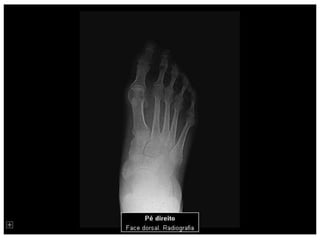

Esqueleto 1

Aula de anatomia acerca do esqueleto Humano 1